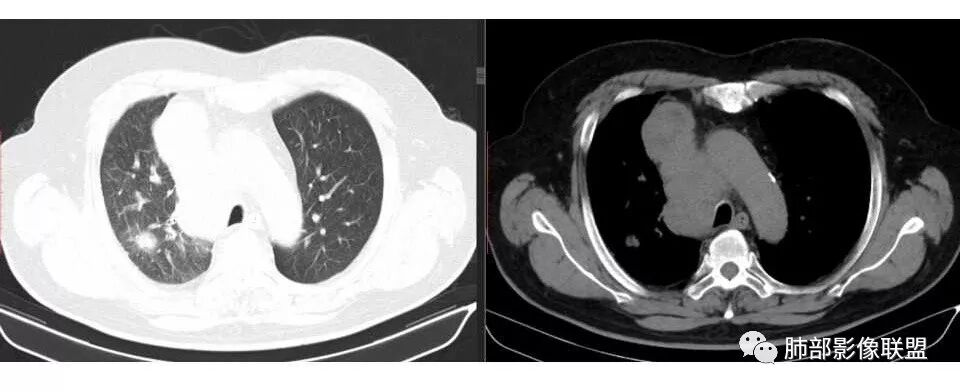

市医院--时建文: 右肺门占位性病变伴纵隔淋巴结肿大,鳞癌?小细胞癌?淋巴瘤待除外,右肺上叶结核。

小溪流: 老年男性,有吸烟史,右肺门及纵隔肿物,考虑鳞癌伴纵隔淋巴结转移,右肺上叶阻塞性炎症。

wkj: 40岁以上吸烟男,右肺上叶新生物,纵隔新生物大于肺新生物,纵隔呈融合,冰冻,气管外压,血管疑似未受累,仅包绕,考虑小细胞。

张帅: 患者以肢体无力就诊,既往有吸烟史,胸CT:右肺门占位性病变,密度不均,病灶内病灶内支气管明显狭窄,走行僵硬,病灶边缘光滑,呈浅分叶,未见明显毛刺,对中叶支气管明显挤压。右肺内可见散在片状实变影,前纵隔淋巴结明显肿大,内可见低密度区,2r 4r 7 10r淋巴结明显肿大。诊断考虑恶性方向,肺癌(小细胞)并纵隔肺门淋巴结转移?淋巴瘤?

水晶石头: 患者中老年男性,以四肢乏力为症状表现,有吸烟史。胸部CT:右肺上叶不规则结节,周围见磨玻璃影,小叶间隔增厚。同侧纵膈明显淋巴结肿大。综合考虑恶性。存在小病灶大转移,冰冻纵隔,且有内分泌症状,首先小细胞癌可能大。监测排外淋巴瘤。

1.右肺上叶不规则结节影,右肺门及纵隔多结节并形成巨大块影,密度均匀,沿途支气管明显狭窄。

原发灶小或隐匿,肺门纵隔淋巴结异常增大,所谓“娘小崽大”常见于肺小细胞癌!